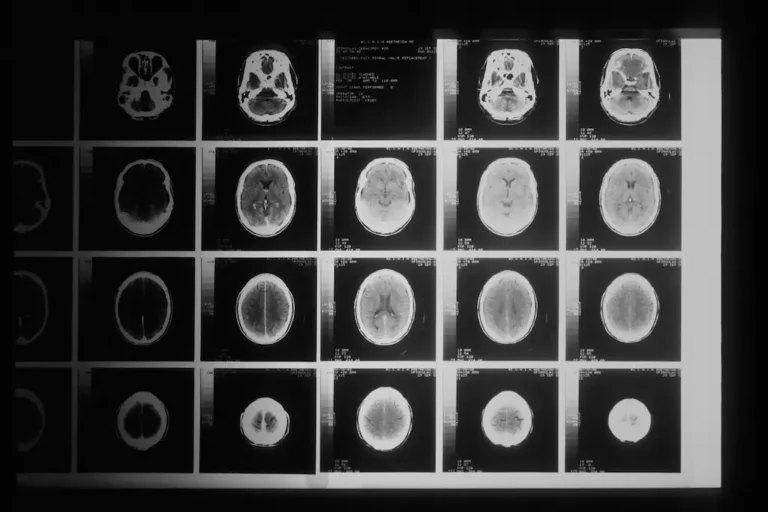

- Diagnostic imaging such as CT scans

Do you handle cases involving CT scans and other medical evidence of brain injuries?

Yes, our attorneys are skilled in handling cases involving CT scans and other medical evidence to prove brain injuries. We work closely with medical professionals to ensure comprehensive representation.